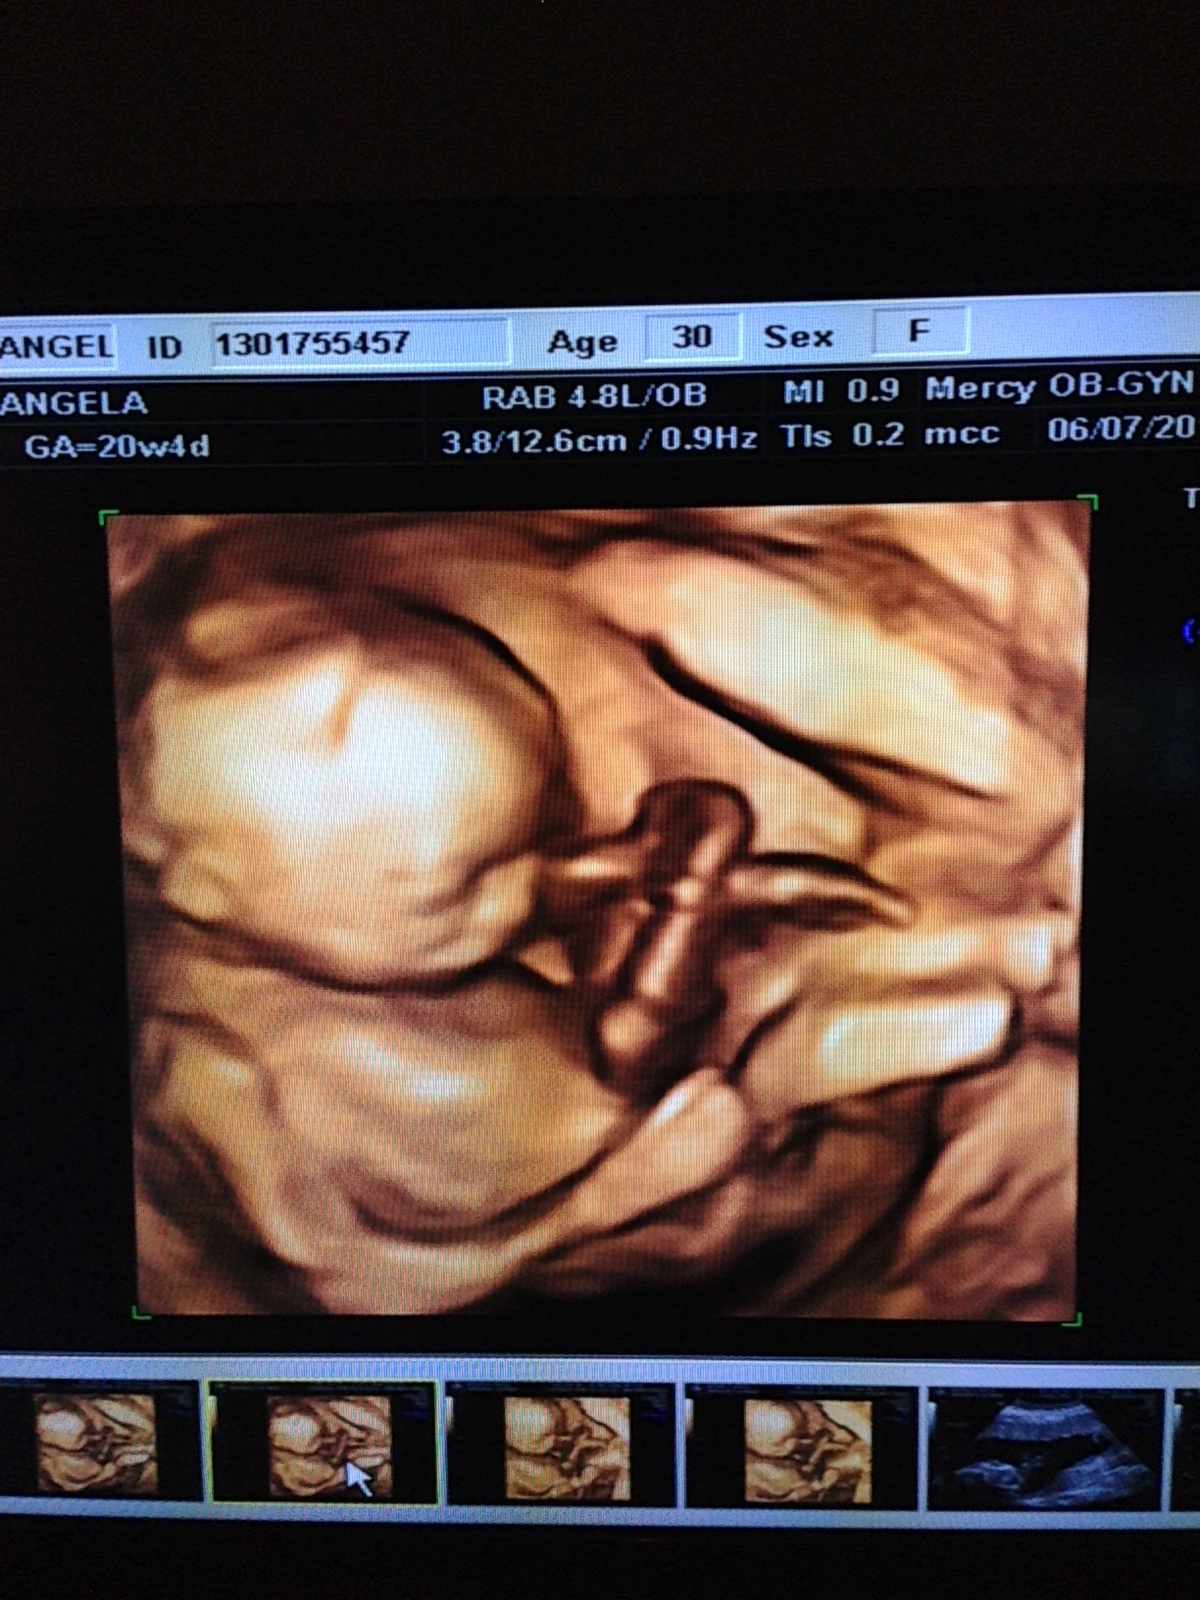

Right now, baby is around 11-12 inches long and weighs about 1 pound. I'm currently 23 weeks along, and at our 20 week appointment we found out that baby #2 is a GIRL! Another healthy, beautiful baby girl :) I am so happy that my girls will get to grow up to be best friends just like me and my sister are.

Here are the best shots from our 20 week ultrasound: